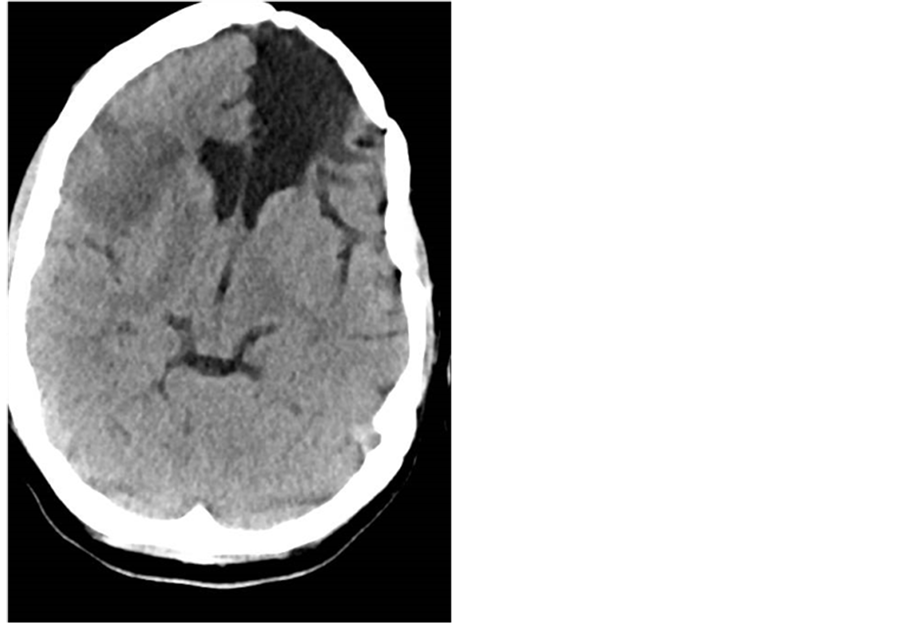

The patient was placed on continuous EEG monitoring, antiseizure medication, and was treated with hypothermia [Figure 1].

Figure 1. Head CT on arrival showing old left frontal encephalomalacia as well as new right MCA ischemia.

After a stat cardiac ECHO showed a left ventricle thrombus and EF < 15%, she was started on heparin and norepinephrine drip. On the second day, she went into cardiogenic shock and was started on milrinone. Her SBP improved but she remained tachycardic. On day four, the patient was weaned off of norepinephrine, but remained on milrinone for one more day. A repeated TTE showed EF of 15% - 20% and more left ventricular thrombi. The patient remained on anticoagulation, the hypothermia protocol was stopped, and the sedation was lifted gradually.